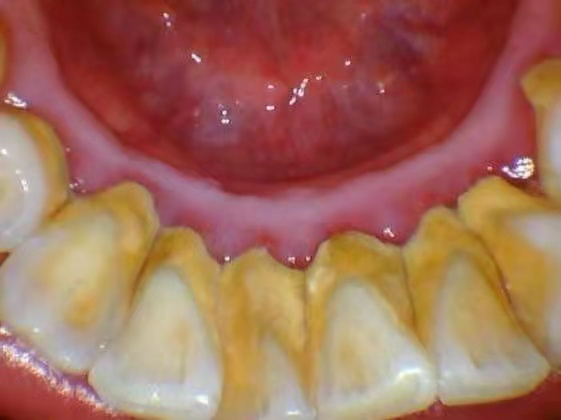

牙石(牙結(jié)石)

牙齦出血的炎癥和出血,牙齦呈現(xiàn)暗紅色或鮮紅色,牙齦腫脹,質(zhì)地松軟

;